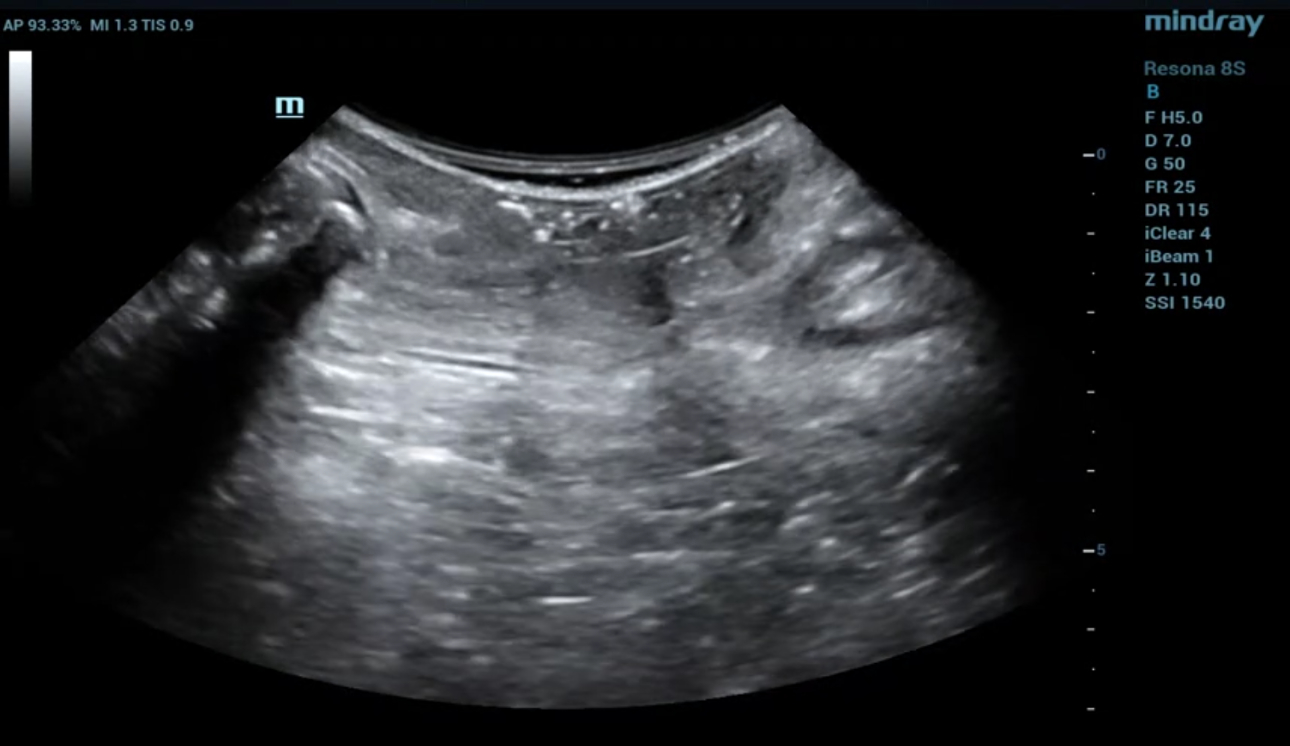

1. 2D 스캔 : 항문거근 섬유에 완전 또는 부분적인 interruption에 의해 절단면이 거칠고 좌우 비대칭 확인.

2. Levator hiatus가 비대칭적이고 부상 방향으로의 이탈 확인.